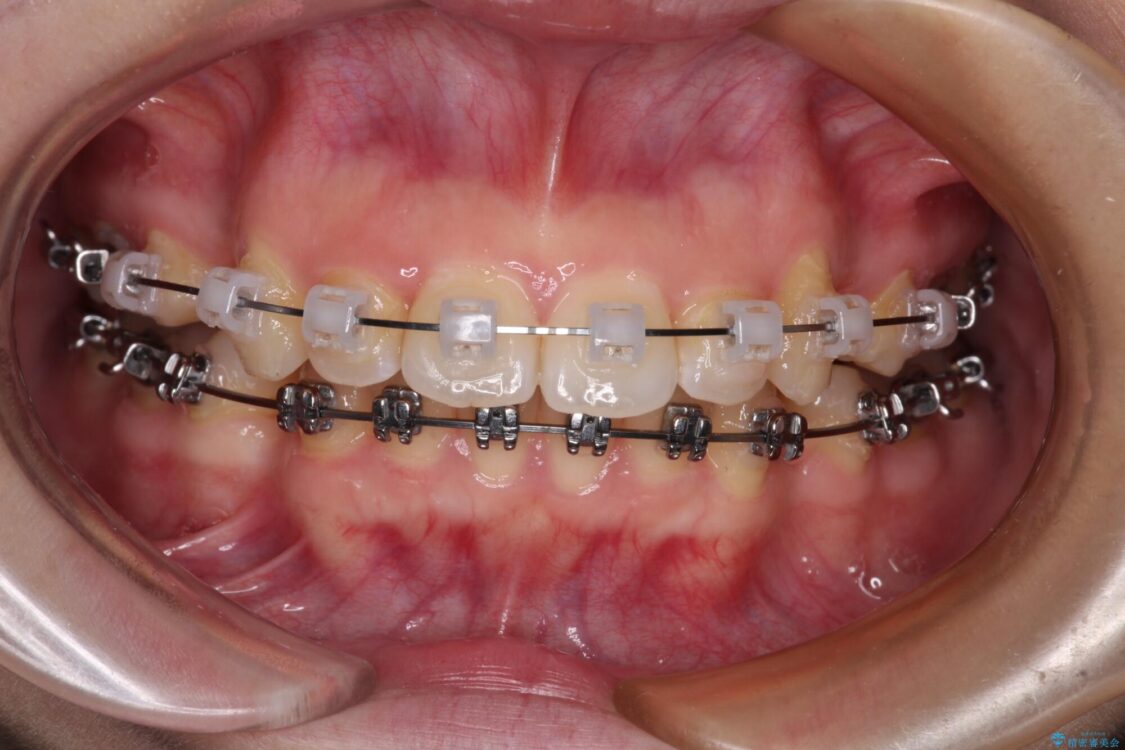

上下前歯が著しく前突している状態であったので、上下左右の第1小臼歯4本を抜歯し、ワイヤー装置にて矯正治療を行うこととしました。

舌の突出癖により、前突になったと考えられたため、舌のトレーニングをしっかりと行うよう指導しました。

※写真にある上顎装置はメタルブラケットではありません。メーカー在庫都合などにより別の装置を使用しております。

治療途中